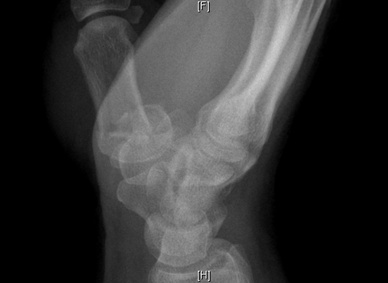

A 40 year old male presents with a painful thumb after crashing his bicycle. On physical exam there is swelling and tenderness around the base of the thumb. What is the diagnosis?